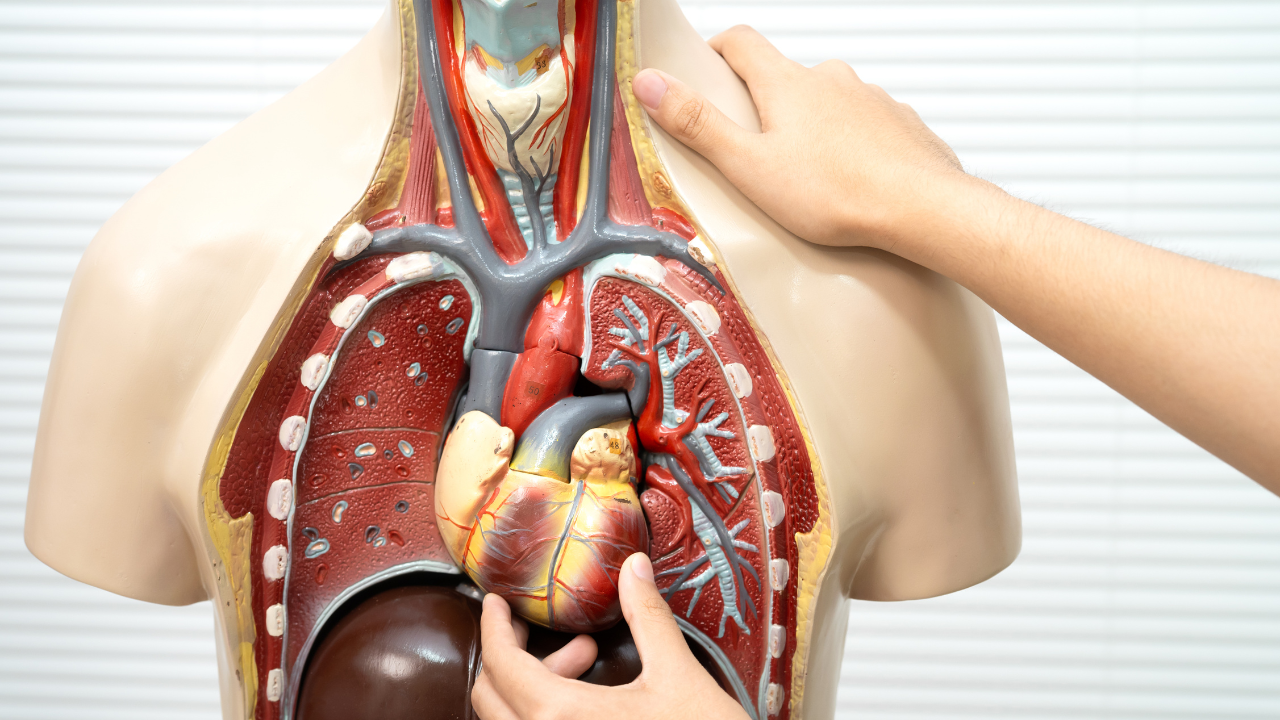

Foods that support your lungs, liver, gut, and eyes

Breathing feels automatic, but lung health depends heavily on what goes into the body. Pollution, stress, and infections can irritate airways. This is where certain everyday ingredients quietly step in.